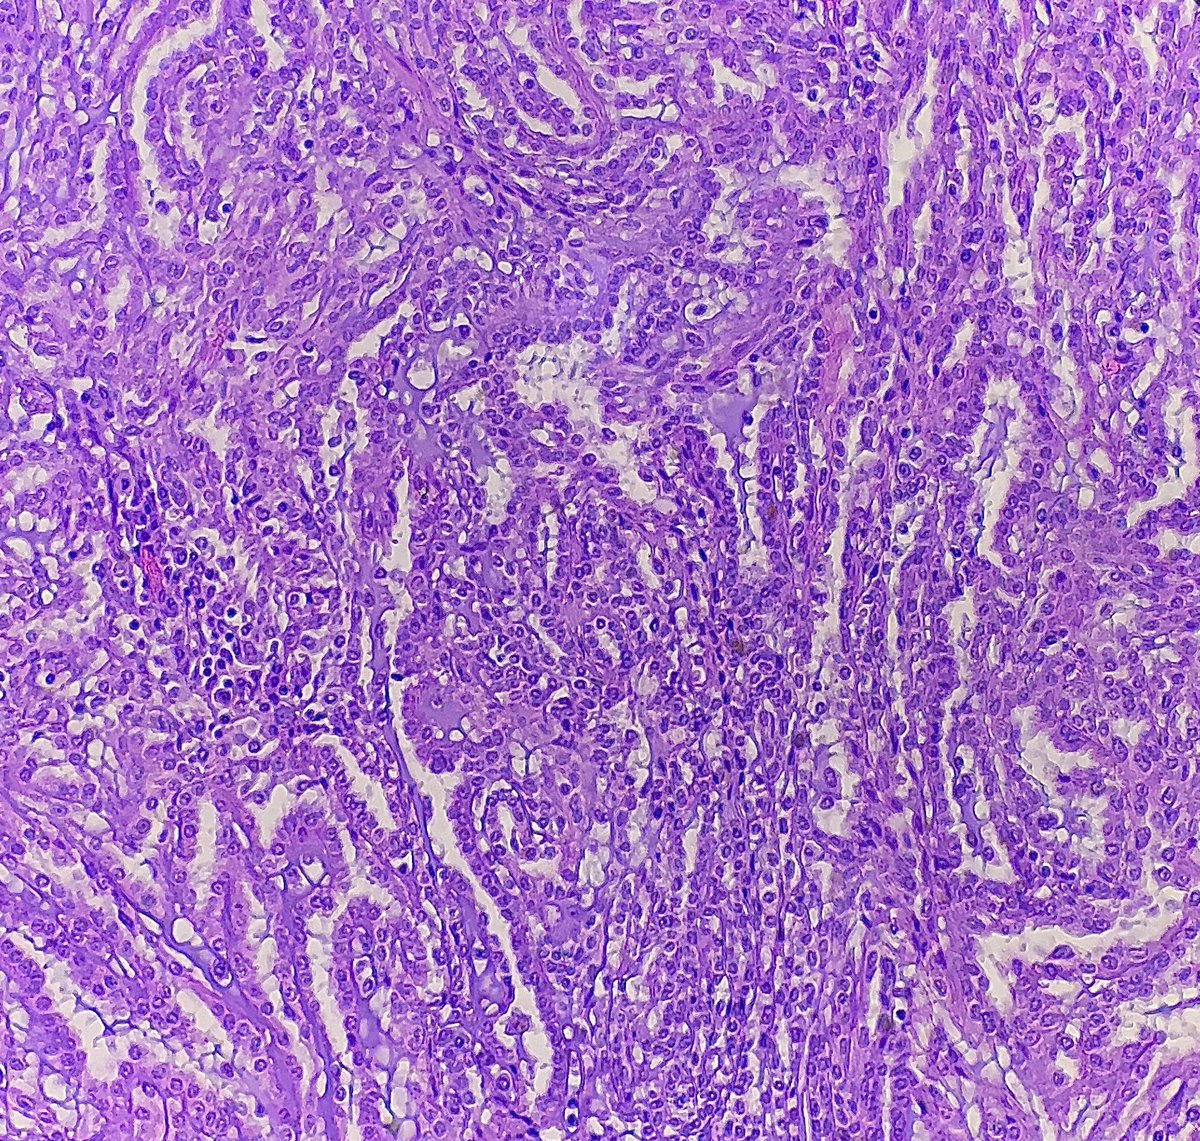

Collision of clear cell renal cell carcinoma and papillary renal cell carcinoma! This #prcc is trying to invade #ccrcc! #PathTwitter #gupath